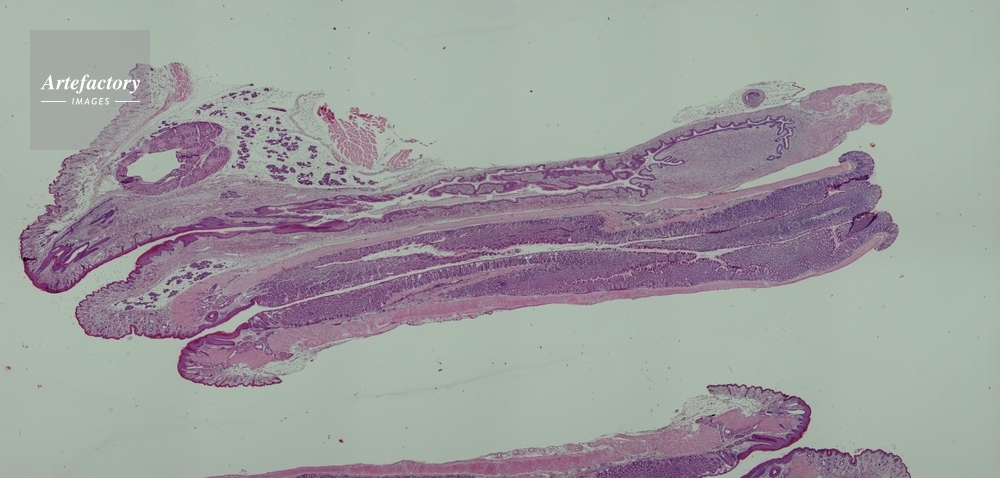

| 作品タイトル | マウス,膣、子宮、直腸 | モデルリリース | なし | |

| キャプション | 合成画像 | 制限事項 | ||